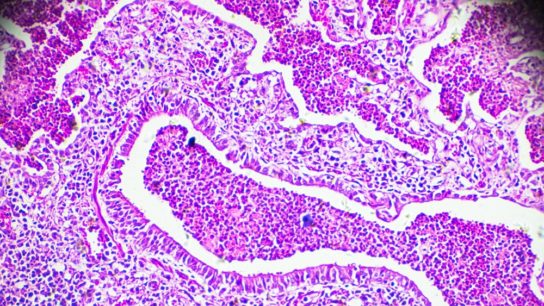

Primary central nervous system vasculitis is an important but rare differential diagnosis in daily neurological practice, warranting the need of a step by step approach.

Researchers sought to highlight several recent advances in the epidemiology, pathogenesis, clinical features, investigation, acute management, and secondary prevention of cerebrovascular diseases in patients with hematological diseases.